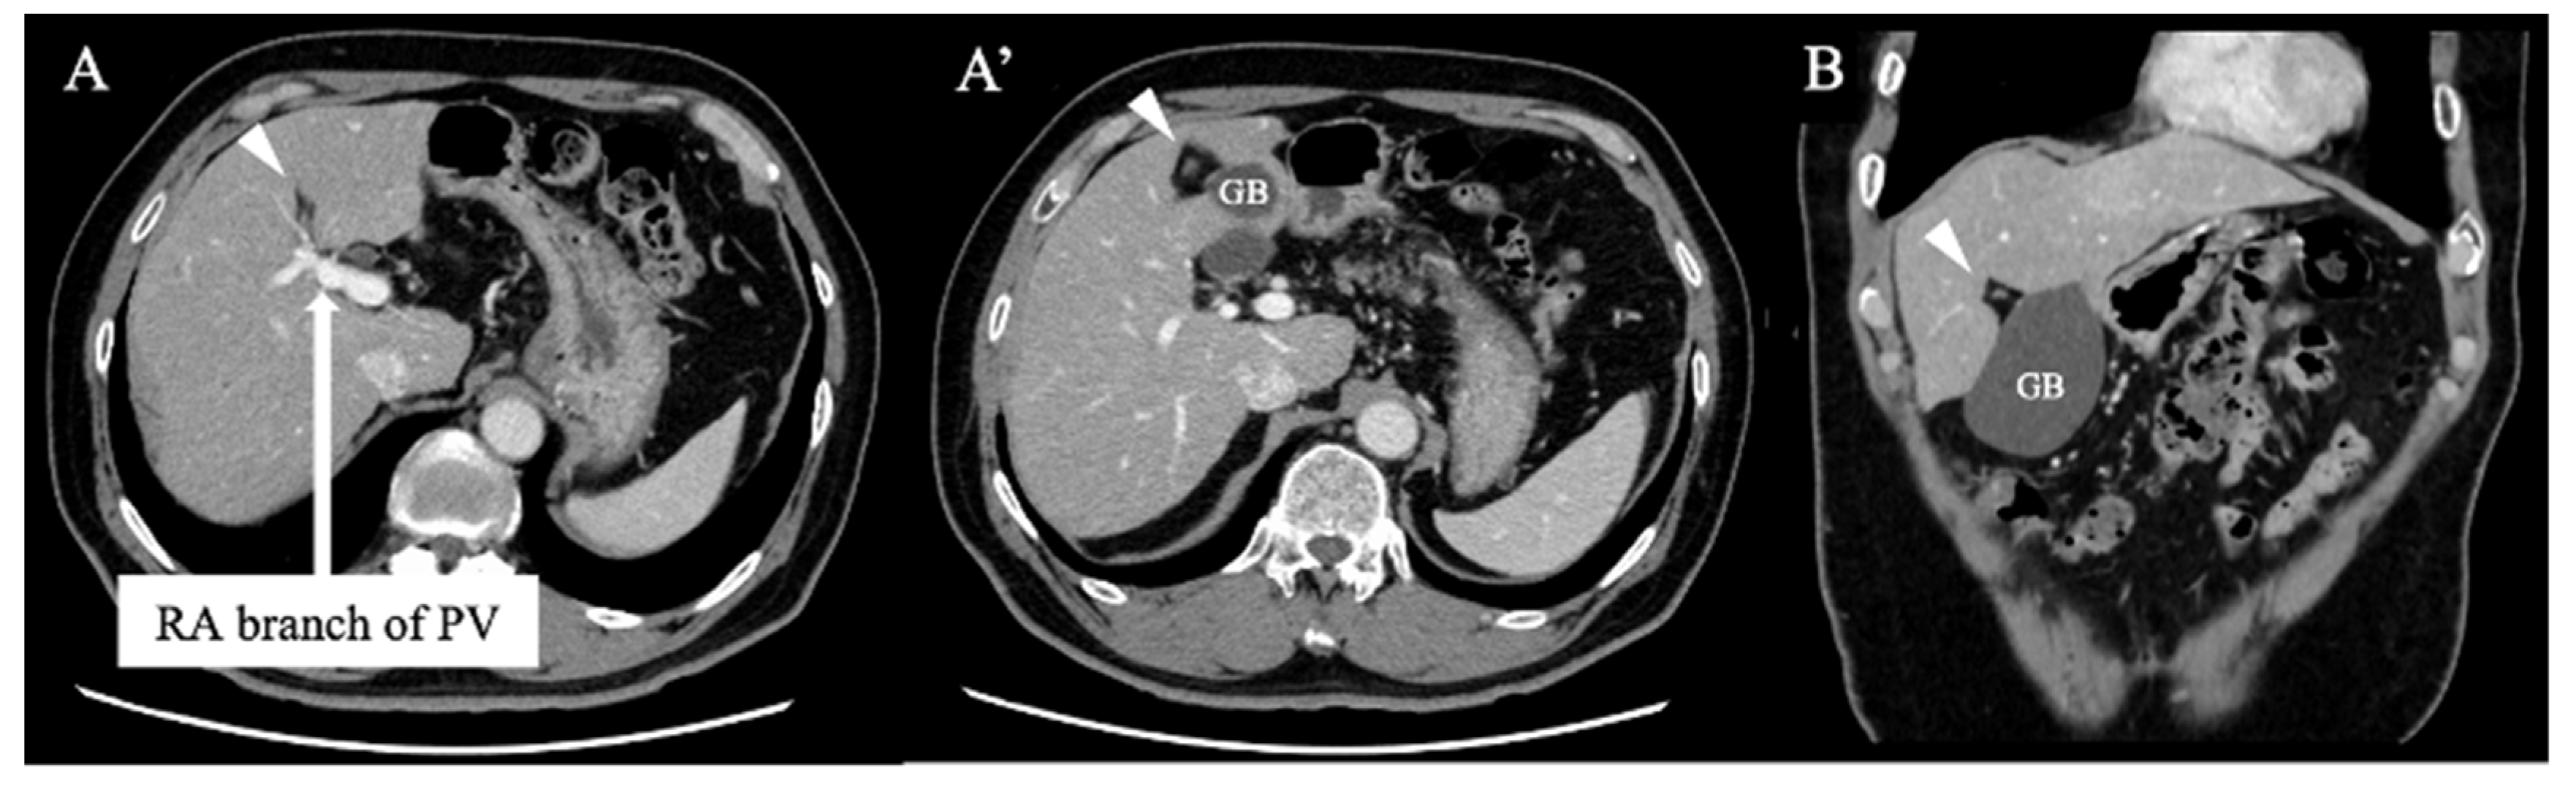

Figure 2. Axial (A and A’) and coronal (B) contrast-enhanced computed tomography demonstrated that the ligamentum teres (arrowhead) was connected to the right anterior (RA) branch of the portal vein (PV) and the gallbladder (GB) was located to its left, indicating right-sided ligamentum teres.

A 69-year-old man was referred for evaluation of a liver tumor detected on abdominal ultrasonography performed for nonalcoholic steatohepatitis follow-up. Blood testing showed elevations in concentrations of aspartate transaminase (56 U/L), alanine transaminase (51 U/L), and protein induced by vitamin K absence-II (224 mAU/mL). Other tumor markers and hepatitis virus markers were negative. The indocyanine green retention rate at 15 minutes was 15.2% and Child–Pugh score was 5 points (class A), suggesting good hepatic function. Computed tomography (CT) showed a 2.4 × 2.0 cm hypodense mass in the left lobe of the liver (S2/3/4b) which exhibited early arterial enhancement and washout (Figure 1). Hepatocellular carcinoma was highly suspected. In addition, the ligamentum teres was connected to the right anterior branch of the portal vein, and the gallbladder was located to its left, indicating RSLT (Figure 2). On magnetic resonance imaging, the mass was low signal intensity on T1-weighted images and high signal intensity on T2-weighted and diffusion-weighted images; contrasted imaging using gadolinium ethoxybenzyl diethylenetriamine penta-acetic acid revealed a perfusion defect in the mass in the liver phase (Figure 3). Three-dimensional CT (Synapse Vincent®︎; Fujifilm Medical, Tokyo, Japan) demonstrated right posterior, right anterior, and left branches of the portal vein. The left branch branched into P2 and P3 after two P4 branches separated. A right inferior hepatic vein and V8 were present (Figure 4). Magnetic resonance cholangiopancreatography revealed that the bile duct system was trifurcated into right posterior, right anterior branch, and left branches (Figure 5). After the pertinent anatomy was clarified and the preoperative evaluation was completed, we elected to perform laparoscopic extended lateral sectionectomy.